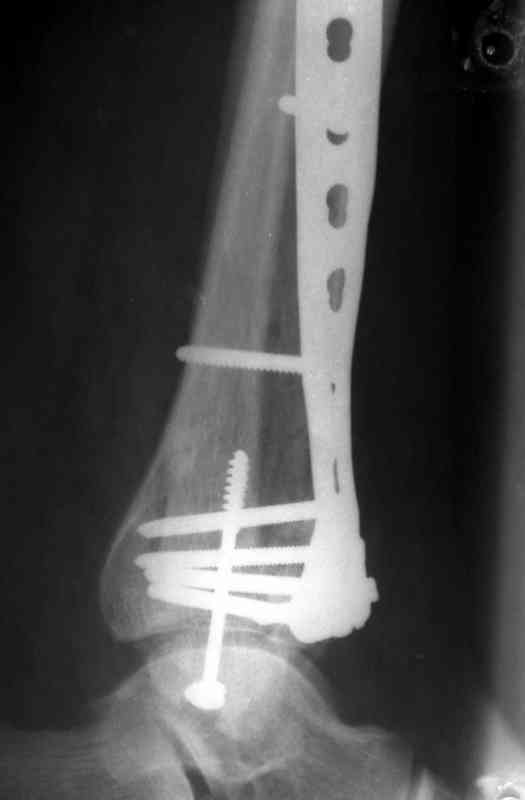

Это типичный перелом пилона, который надп лечить только открыто.Извини те что опоздал к обсуждению, но даже если вы уже оперировали больного по Илизарову это даже лучше.Посылаю картинки.

Посмотрим вроде прошло если понравится напишите расскажу как это сделать.По принципам АО кстати при поступлении сначала восстанавливают длину малоберцовой кости фиксируют пластиной 1/3 трубки потом накладывают аппарат наружной фиксации и через 7-10 дней открыто восстанавливают большеберцовую кость.С уважением Дрягин

На рентгенограммах типичный перелом пилона по типу С-3. есть опыт до 100 открытых опреаций у нас в клинике. 20 примерно в год. Принцип один -все внутрисуставные переломы нуждаются в открытой репозиции и внутренней стабильной фиксации. При поступлении КТ не надо, так как получается только нагромождение костей. Истинной картины нет. Главное восстановить длину малоберцовой кости - это ключ к успеху. При поступлении меньше всего надо думать о сосудистых расстройствах, т.к. сама операция и репозиция даже сначала частичная даёт улучшение сосудитых нарушений. Причём очень быстро. Операция в 2этапа. При поступлении доступ позади наружной лодыжки, причём обязательно. После этого репозиция малоберцовой кости и фиксация пластиной 1/3 трубки под винт 3,5. Дренаж и любой аппарат наружной фиксации. Затем после спадения отёка на 5-7-10 день аппрат снимается и дугообразный разрез спереди от медиальной лодыжки 10-12 см. Главной чтобы расстояние между 1 и вторым разрезом было не меньше 7-8 см. Тогда не будет некрозов лоскутов. Таранная кость используется как матрица на неё укладываются отломки и фиксируются пицами. Ренг-контроль. Отломки лежат все отдельно, но ничего не высыпется. При переломах С-3 всегда нужна костная пластика (из крыла). Фиксация пластиной лист клевера простой или LCP. Гипс не нужен. Дренаж до 48 часов. Операция длится 3-4 часа обязательно без жгута. Посылаю примерно такой же случай.

Послала ещё два снимка, если не пройдут, пошлю ещё. Дрягин. Если есть вопросы, готов ответить.

Посылаю результат лечения предыдущего больного через год.